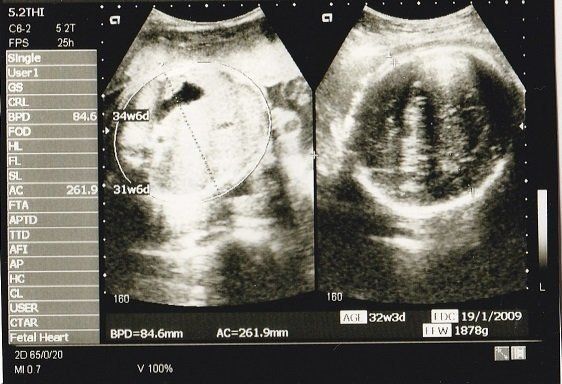

妊娠32週目のエコー写真 おなかもぱんぱんです。

AC(おなかの周囲の長さ)などから、赤ちゃんの推定体重を計算するようです。赤ちゃんのおなかも大きくなっていますが、お母さんのおなかもぱんぱんです。